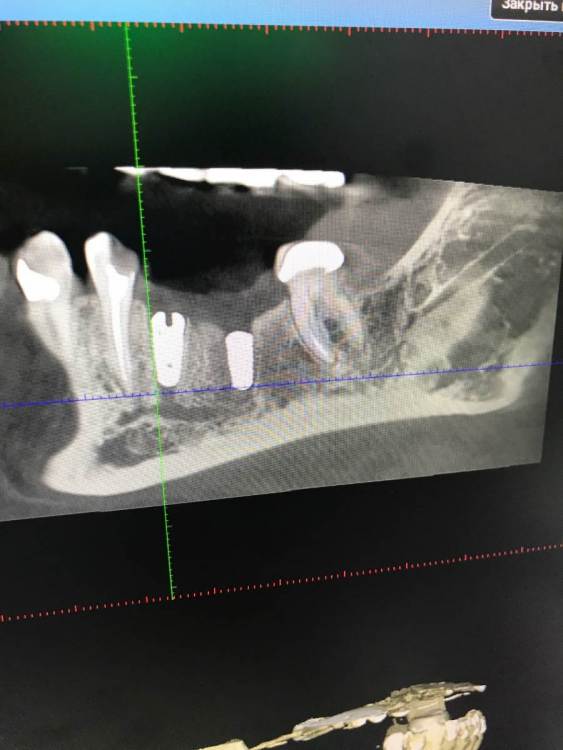

chealena Опубликовано 14 августа, 2021 Поделиться Опубликовано 14 августа, 2021 Здравствуйте ! В среду мне установили 4 импланта по две на каждые стороны нижние, слева также удаляли зуб и туда сразу ставили имплант. После этого у меня сейчас онемевшая губа и часть зубов и часть подбородка, что мне делать? Врач говорит что все нормально и нерв не был задет, а я вижу что на кт снимке идёт траншея до нерва , как будто он просверлил туда. Говорит мне ничего не делать и просто ждать. Но онемение не проходит, уже и отёк спал , а онемение есть и это ужасно противно, и когда пальцем вожу по этому месту очень неприятно как будто песок. Зуб слева первый имплант на снимке. Подскажите пожалуйста что делать! Ссылка на комментарий

Irouil Опубликовано 14 августа, 2021 Поделиться Опубликовано 14 августа, 2021 Как и что могло случится - это спрашивать стоит только у того человека, который видел своими глазами что и как случалось. Иначе говоря, эти вопросы надо задавать лечащему врачу. Выкручивание имплантов, судя по предоставленным снимкам, никак не повлияет на ситуацию с онемением. Но это не отменяет Вашей симптоматики, а значит какое-то влияние на нерв есть. Неврологическая терапия поможет снизить это влияние и ускорить процесс восстановления чувствительности. Ссылка на комментарий

Irouil Опубликовано 16 августа, 2021 Поделиться Опубликовано 16 августа, 2021 15.08.2021 в 00:45, chealena сказал: Но если нерв не поврежден почему у меня пол губы немые вместе с подбородком и частью зубов? Воздействия на нерв не ограничиваются только его повреждениями. Даже отёк от проведённой операции способен создать иногда достаточную компрессию чтобы вызвать транзиторную парестезию. Импланты в канал не пенетрируют, это самое главное. Руками хирурга тут особо нечего изменить/исправить. Применение физиотерапевтических процедур может ускорить реабилитацию. 2 Ссылка на комментарий